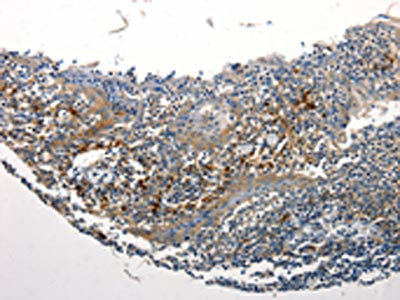

The image is immunohistochemistry of paraffin-embedded Human tonsil tissue using CSB-PA105672(STAT5B Antibody) at dilution 1/25. (Original magnification: ×200)